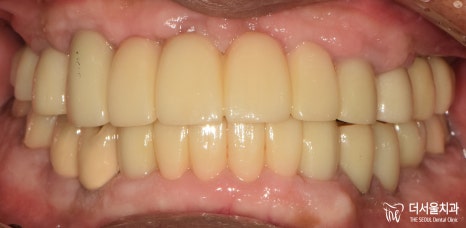

6. 최종 결과

완성된 보철을 전달받은 뒤,

그렇게 최종 보철을 세팅하며

꼼꼼하게 조정하고 마무리 지었는데요.

실제로 적용된 모습을 보면,

이전에 있던 진짜 치아랑 별반 다를게 없죠?

기능, 심미성 모두 신경써서

만들어드렸습니다.

이제 마음껏 식사를 즐기고

다른 분들과 즐거운 대화도 나눌 수 있게 되었는데요.